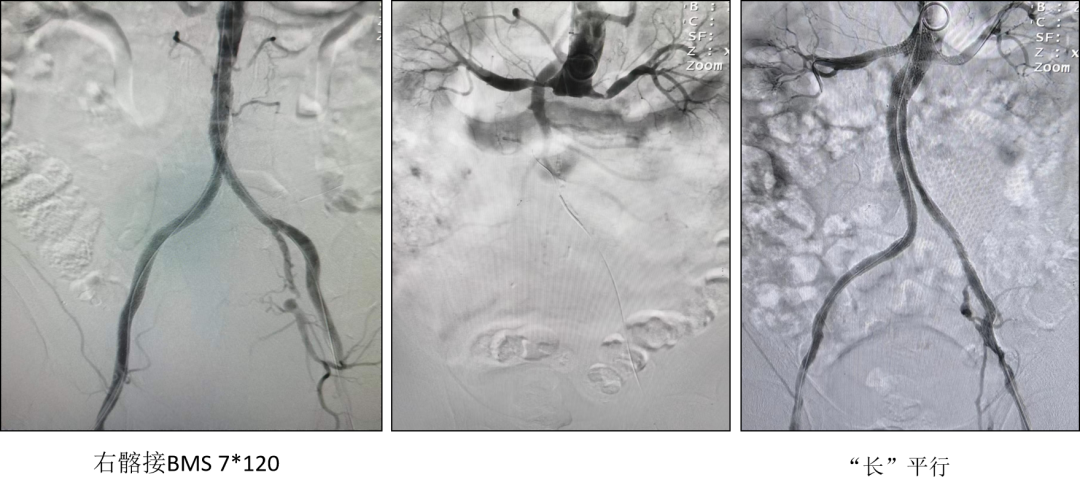

“长”平行

典型病例:展示了双侧髂总动脉重度狭窄的病例,通过CERAB技术成功重建。

A.造影提示双侧髂总动脉重度狭窄

B.双侧髂总动脉VBXTM Kissing 植入(箭头处为重度钙化)

C/D. 造影提示双侧髂动脉复通,支架顺应原动脉扭曲

男,73岁,双下肢冷感伴间歇性跛行2年余,加重20余天